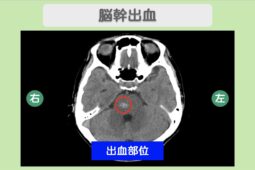

外傷性くも膜下出血

「外傷性くも膜下出血」とは、頭を打ったことにより、くも膜と脳の間で出血が広がった状態です。

くも膜下出血の多くは脳動脈瘤(血管の一部が「こぶ」のようにふくらみ、破れやすくなった状態)によるもので、頭を打った場合は区別して外傷性くも膜下出血と呼びます。

基本は入院での経過観察で、脳圧が高くなる場合は投薬や手術などを行います。